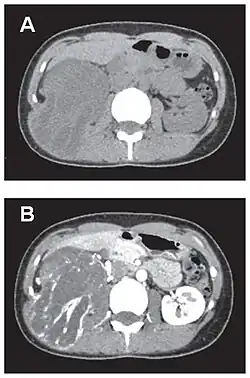

En tomodensitométrie[20],[31], quelle que soit la localisation, une tumeur fibreuse solitaire apparaît comme une masse tissulaire ovoïde ou lobulée, bien délimitée, refoulant les structures voisines sans les envahir. Elle se rehausse fortement après injection de produit de contraste. Les tumeurs de petite taille sont homogènes, mais les plus volumineuses présentent des plages hétérogènes de nécrose et d'hémorragie intra-tumorale. Il n'y a pas habituellement de calcifications et, lorsqu'elles sont présentes, elles sont de petite taille[31]. Les tumeurs malignes peuvent se présenter accompagnées de nodules pulmonaires métastatiques, et tendent à être plus volumineuses et plus hétérogènes[42].

- Tumeur fibreuse solitaire du rétropéritoine

Aspect tomodensitométrique, sans (A) puis avec (B) injection de produit de contraste[44].